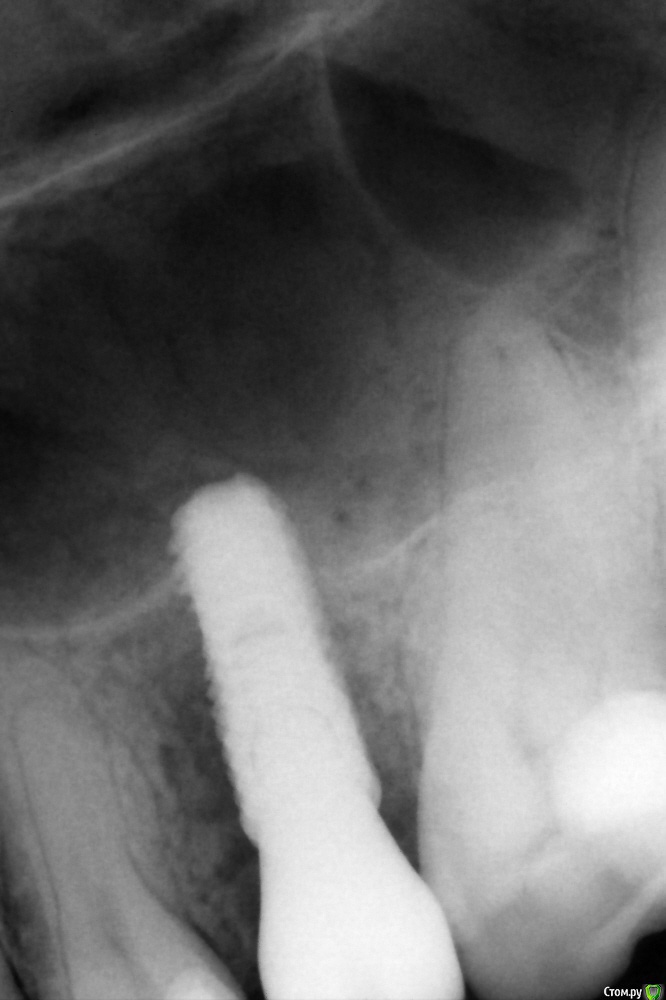

колесников Опубликовано 10 апреля, 2016 Поделиться Опубликовано 10 апреля, 2016 Бюджетная была работа. Без графта,без прф,без сст. Удаление 25 с дефектом кости и в период обострения. Через 3 мес имплантация (осстем 4.0х11.5) и закрытый синус без графта (пациент не потянул). Решил проверить на сколько нарастёт кости чисто на сгустке, при поднятии мембраны на 3-5 мм (не ровное дно). Торк был 35-40 -фдм сразу. Гребень остался широким,сст не стал подшивать,перекинул лоскут с гребня. Через 5 мес наросло 2-4 мм. 5 Ссылка на комментарий

колесников Опубликовано 11 апреля, 2016 Автор Поделиться Опубликовано 11 апреля, 2016 как гранулемку убирали и как контролировали,или с корнем ушла ?кстати синус она сделала не неплохой)))Выскабливанием убрал. На орто не объективная картина,накладывается вестибулярное "окно" гранулёмы. До дна 1мм + 1мм дна. Вестибулярная стенка была перфорирована. Ссылка на комментарий

колесников Опубликовано 14 апреля, 2016 Автор Поделиться Опубликовано 14 апреля, 2016 Прям уж закрытый синус? По фото - элементарная бикортикальная фиксация имплантата. Главное - не хамить с пазухой, ибо , торчащий сквозь слизистую винт - прекрасная база для колонизации грибов.Закрытый-это когда закрытый. Отодвинул мембрану через лунку . На снимке видно что имплант не зияет в пустоте и притоплен субкрестально. Ни с какой стороны на бикортикальную не тянет. И кстати про хамить и колонизацию(фамилии не вспомню,может кто поможет),на конференциях часто встречал снимки итальянского спеца -любителя поставить имплант в пазуху на 10 и более мм без прикрытия. 1 Ссылка на комментарий

колесников Опубликовано 14 апреля, 2016 Автор Поделиться Опубликовано 14 апреля, 2016 Согласен с предыдущим комментарием...это бикортикальная фиксацияНе соглашусь. Хотя у меня и не кт,крыть нечем,но видно что над имплантом тень,т.е. он не зияет изначально. И без полипов в итоге-значит имплант не находился в утолщённой шнейдеровой. У вас ,кстати, ведь тоже 3-4 мм наросло? Ссылка на комментарий